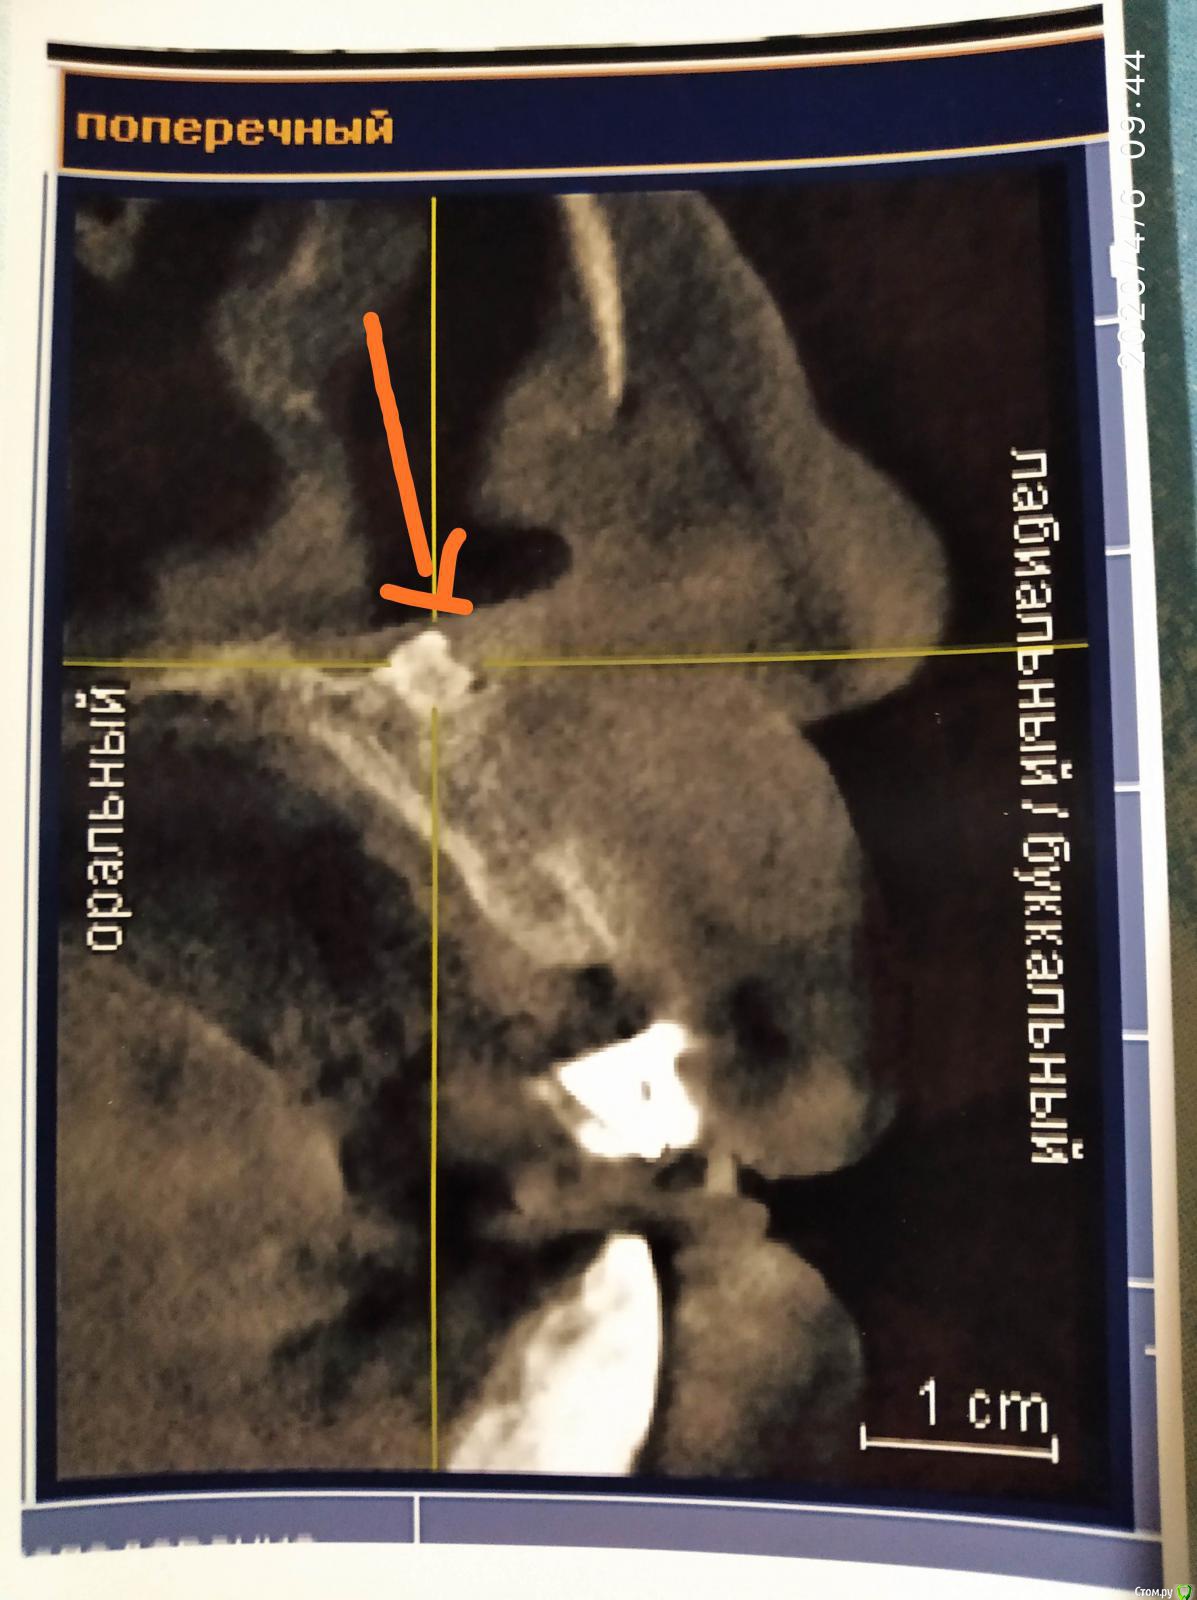

Алексей870 Опубликовано 6 апреля, 2020 Поделиться Опубликовано 6 апреля, 2020 Здравствуйте помогите разобраться образование в верхней челюсти возле резцового канала ..в 2000 году давно мне ставили штифт в верхнюю двоику на снимках этот зуб удален уже и после лечения зуба начало закладывать нос аллергия боли лицевые .сделал КТ челюсти там обнаружилось образование .в 2015 году челюстно лицевом хирург попытался удалить но не долез до него достал только как он сказал вату с челюсти откуда она там взялась...есть мысли что стоматолог что-то мне туда загнал в челюсть .. Ссылка на комментарий

Bier Опубликовано 6 апреля, 2020 Поделиться Опубликовано 6 апреля, 2020 похоже на пломбировочный материал, он высоко, прямо под носом. Но удалить можно Ссылка на комментарий